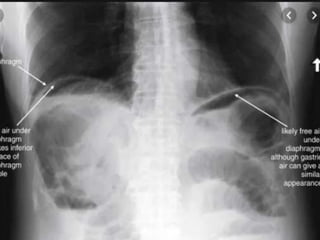

ABDOMINAL PLAIN

RADIOGRAPH

 Gas filled, dilated small bowel loops with air fluid

levels.

 Thumb printing sign (thickening of bowel wall +

valvulae (edema)

 Pneumatosis intestinalis.

 Mesenteric + portal vein gas

ABDOMINAL PLAIN RADIOGRAPH  Gasfilled, dilated small bowel loops with air fluid levels.  Thumb printing sign (thickening of bowel wall + valvulae (edema)  Pneumatosis intestinalis.  Mesenteric + portal vein gas